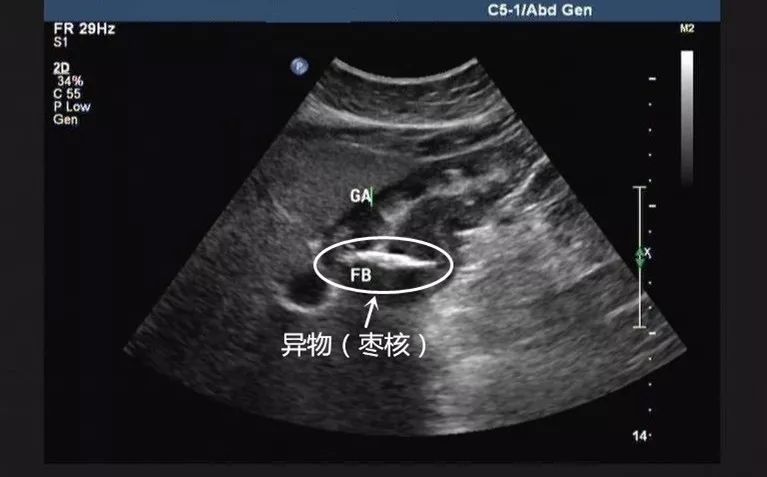

胃内异物伴胃窦部胃壁增厚: